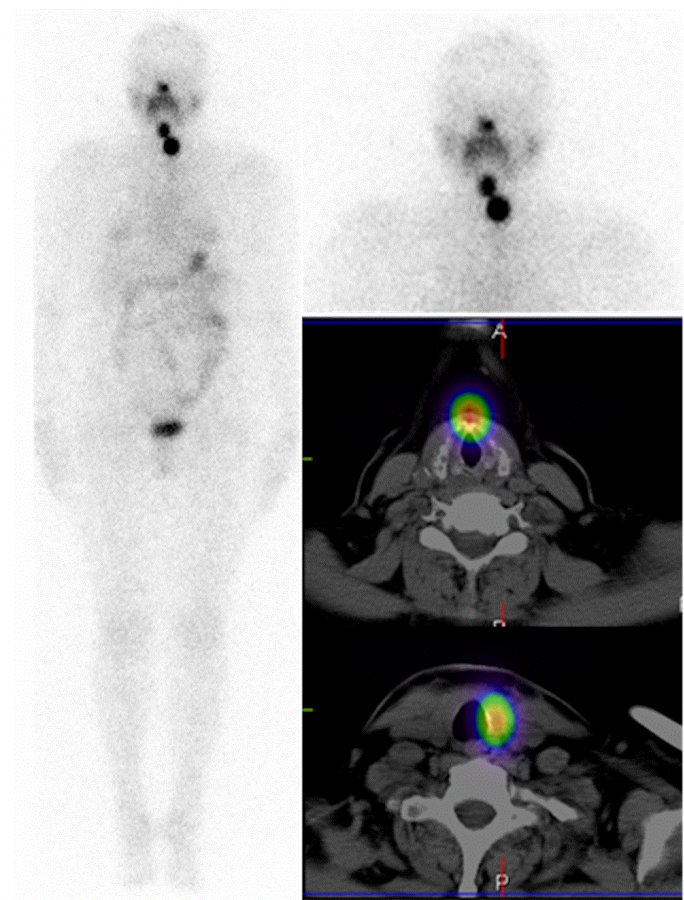

Przykładowe obrazy scyntygraficzne uzyskiwane w naszym Zakładzie Medycyny Nuklearnej: